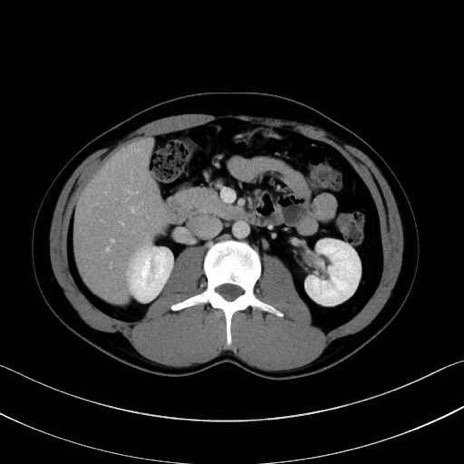

【症例】20歳代 男性 スクリーニング

脾動脈の画像解剖

■起始:典型的には腹腔動脈幹(celiac trunk)から左胃動脈・総肝動脈とともに三分岐し、脾動脈は左後上方へ向かう。

■走行:膵上縁または膵実質背側を蛇行しながら左方へ進み、膵尾部近傍で脾門へ至る。蛇行の程度は個体差が大きい。

■終枝:脾門部で複数の終末枝に分かれ、上極・下極枝や脾門枝群を形成する。胃短動脈群や左胃大網動脈はしばしば脾動脈から分岐する。